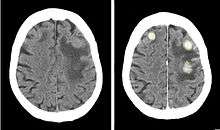

Iodinated contrast is a form of intravenous radiocontrast (radiographic dye) containing iodine, which enhances the visibility of vascular structures and organs during radiographic procedures. Some pathologies, such as cancer, have particularly improved visibility with iodinated contrast.